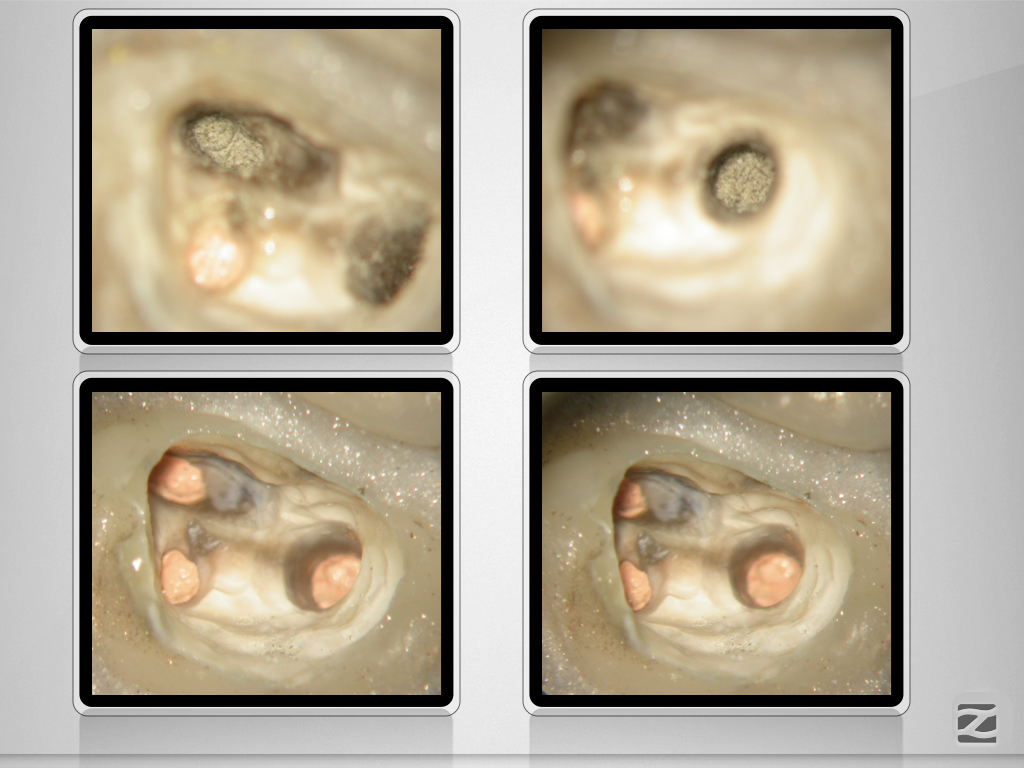

27D.005 Veröffentlicht 18. Januar 2020 am 1024 × 768 in Wer hat Angst vor’m bösen Stift? Teil 1 , Metallstift